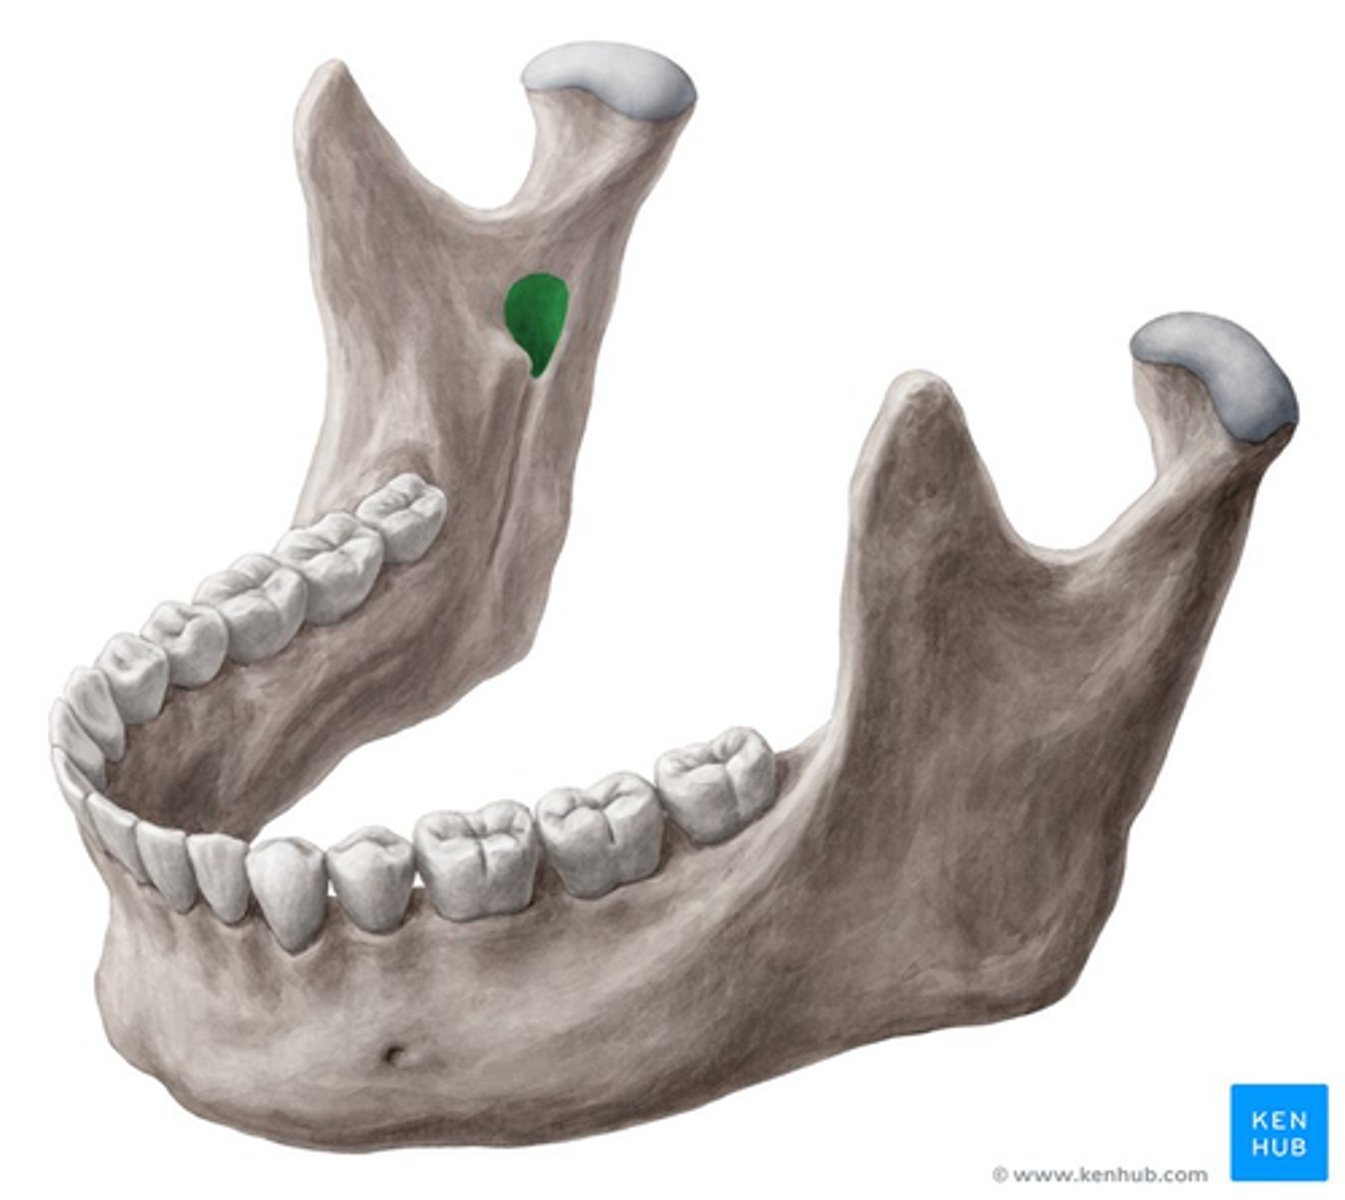

coronoid process

head of mandible

mandibular foramen